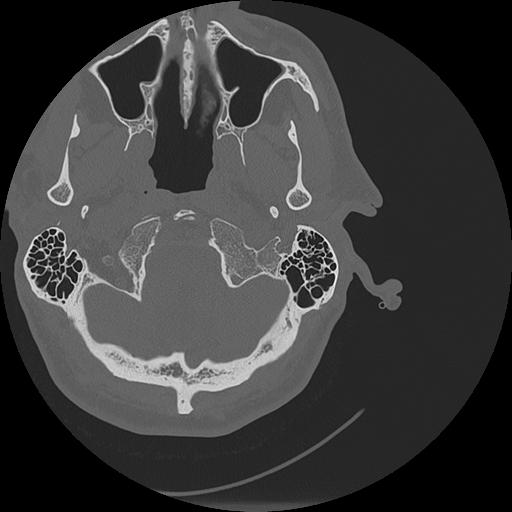

7 HUESO,,Vol,0.5,HUESO,,